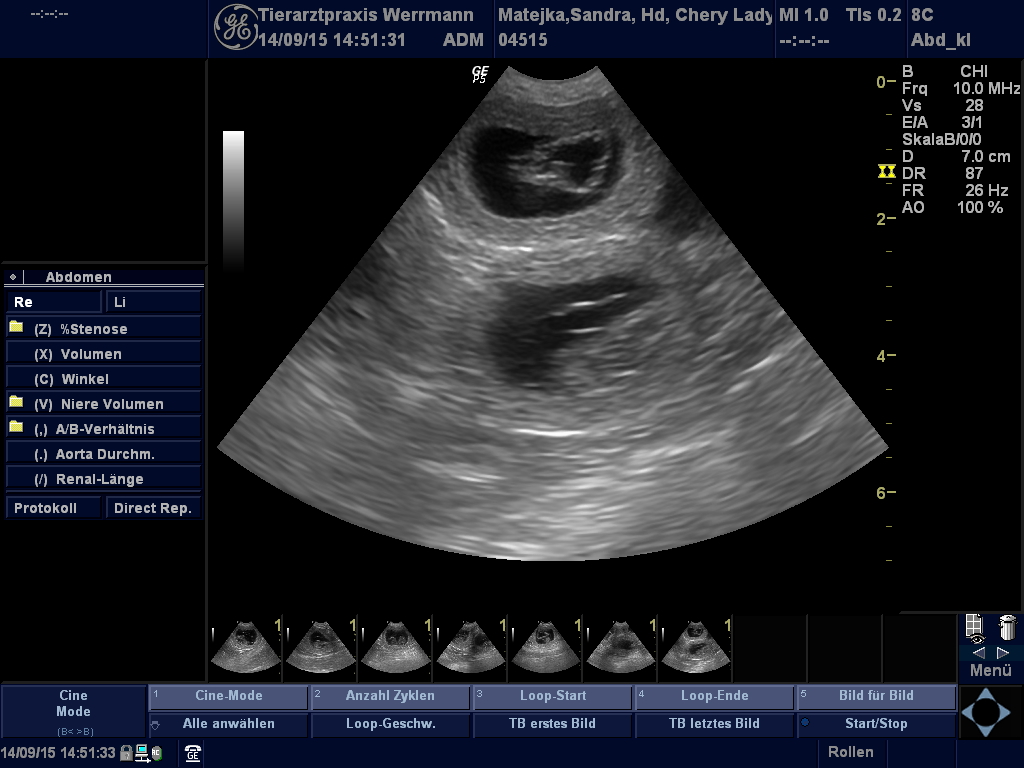

Ultraschallbilder